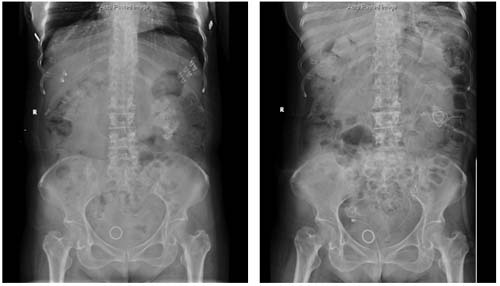

手术前后KUB对比

患者为65岁女性,反复腰痛和血尿多年,经我院检查诊断为左肾铸型结石。患者患有20余年糖尿病病史、严重冠心病且1年前行冠脉搭桥术。为最大化清石且尽可能减少患者的手术创伤应激,陈修德主任医师团队进行了反复、周密的术前讨论和准备,最后决定行可视针孔肾镜辅助治疗肾脏铸型结石,手术效果完美,实现一期完全清石并顺利出院!